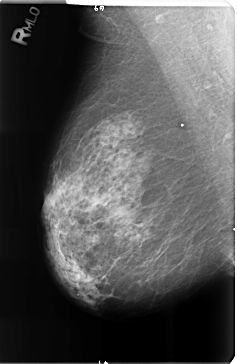

B_3514_1.RIGHT_MLO

RIGHT_MLO LINES 4720 PIXELS_PER_LINE 3072 BITS_PER_PIXEL 12 RESOLUTION 50 NON_OVERLAY